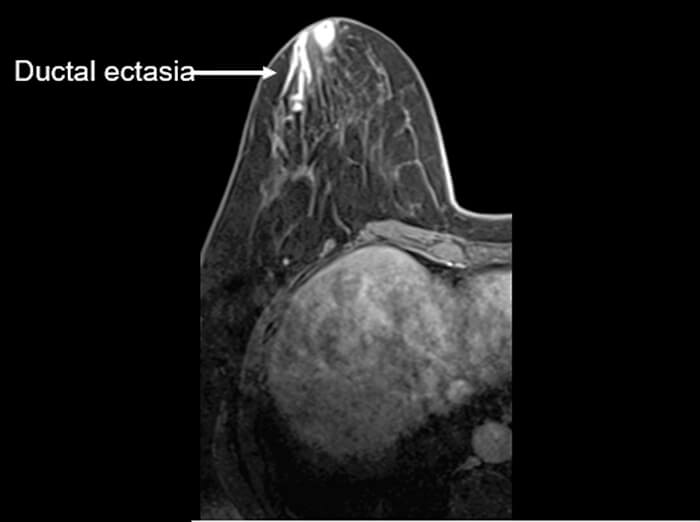

As you know previously, the metaphor of the dance club. The signal must be greater than the background noise in order to be heard. Here we have an image of the breast with a pathology called ductal ectasia. While we can see that there is an abnormality, especially the borders. This is important. If there was a small lesion present, the noise may completely obscure it.

Significance of High SNR

As you can see it is much easier to see the anatomy get a full appreciation of the weighted contrast in images with good signal to noise ratio. We can also get a lot more information about the pathology and the extent of the pathology. Doesn’t this image look much better than the one on the last slide.